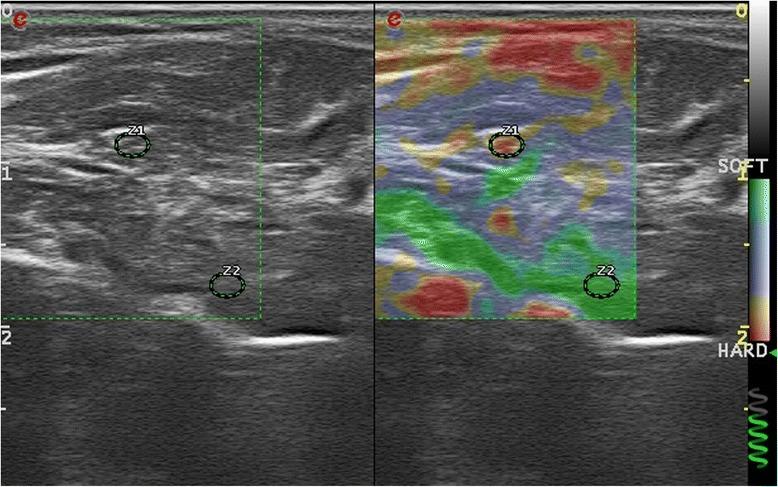

The clinical, electrophysiological and ultrasonographic assessments were done. Patients with SSC and CTS were assessed with nerve conduction studies. The measurements of cross sectional areas (CSA) were performed at psiform and forearm level from axial US images. The elastic ratio is the ratio of strain distribution in two selected region of interests (ROI) done via comparing the median nerve to flexor digitorum superfcialis tendon. The ROIs were fixed to 2 mm.

The study was completed with 47 hands of 24 patients with SSC, 53 hands of 27 patients with CTS and 38 hands of health controls. The CSA of CTS group was significantly higher than systemic sclerosis and control groups. The elastic ratio at psiform level and forearm levels of systemic sclerosis group were significantly higher than the CTS and control groups.

Median nerves lose the elasticity while the CSA's are in the normal range in patients with SSC. These results suggested that the increased peripheral nerve involvement in SSC is about the increased stiffness of the nerves.